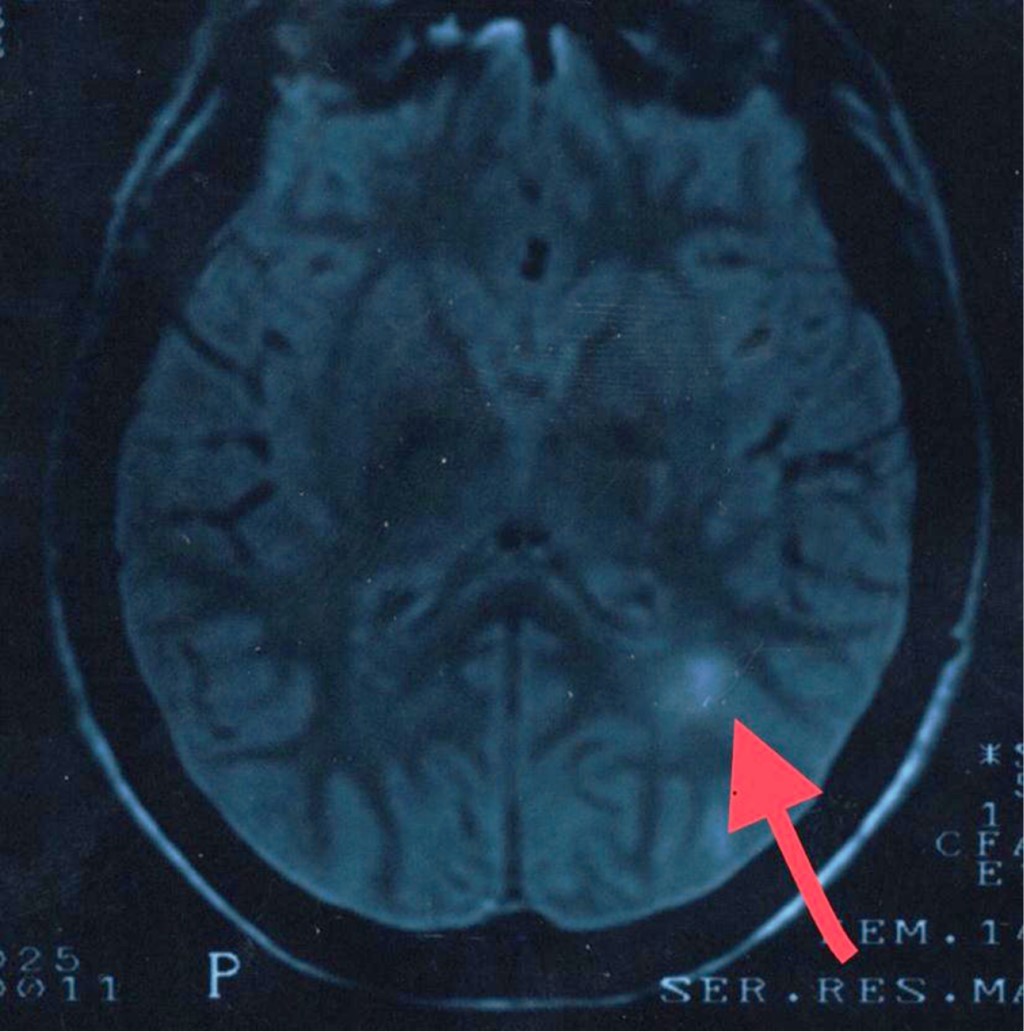

Objective: We describe two adolescent patients with multiple sclerosis, which is a demyelinating disease of the central nervous system. Presentation of the cases: The first case was a 14-year-old female patient with overweight; her condition was characterized by dizziness, headache, paresthesia in the lower limbs, diplopia and bradylalia. On physical examination, compatible data of cerebellar involvement were identified. A magnetic resonance imaging (MRI) of the skull showed areas of demyelination in the posterior fossa. Multiple sclerosis, the relapsing-remitting variety, is diagnosed. After the administration of steroids and beta interferon, there was improvement in symptoms. Second case: 13-year-old female, who presented fall from her own height, bladder incontinence, loss of strength in the left arm and leg. On physical examination, left hemiparesis was detected. MRI: demyelination data in lateral ventricle, cerebellum and spinal cord. The patient improved after starting steroids and interferon. Conclusions: The clinical presentation of multiple sclerosis in pediatric patients is a challenge, since it is a condition with unspecific manifestations. Establishing the diagnosis requires multiple studies. The earlier treatment is started, the more favorable the prognosis.

Figure 2